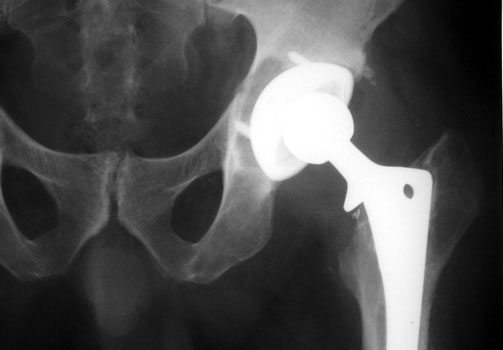

OSTEOLYSIS

Multifocal and massive, involving Gruen zone III of acetabular cup and Grune zone 1,2, and 6 of femoral component